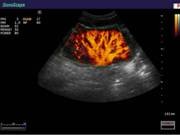

В Центре современных медицинских технологий «АКВА МЕД МАРИН» прием ведет врач УЗД высшей категории со стажем более 20лет - Пахалюк Александр Александрович. УЗИ-диагностика проводится на новейшем ультразвуковом диагностическом сканере Экспертного класса SonoScape S40Exp, в том числе и УЗИ детям с применением специальных детских датчиков. Цветной допплер помогает точной диагностике патологии сосудов и сердца у взрослых и детей.

Компания SonoScape уделила особое внимание допплеровским режимам и является экспертом в своем классе, что позволяет с легкостью, но в то же время с уникальной точностью проводить исследования с постановкой наиболее точного диагноза.

Ультразвуковые исследования, доплеровское сканирование сосудов в Центре современных медицинских технологий «АКВА МЕД МАРИН» выполняется при помощи первого и единственного аппарата в Керчи SonoScape S40Exp (экспертного класса, который оснащен множеством новейших функций, многократно улучшающих качество и информативность УЗИ-исследования).